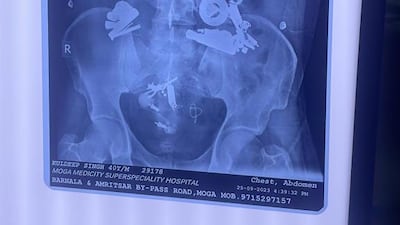

Doctors conducted X-ray scans which revealed metal objects lodged inside his stomach.

They immediately operated and during a three-hour surgery retrieved earphones, a bracelet, nuts and bolts, wires, lockets, buttons, wrappers and safety pins from his stomach.

“There was a ball of foreign objects that we call radiopaque materials. After surgery, we found 150 articles including bracelet, zipper, nails, nuts and bolts. He was in pain for nearly a week,” he said.